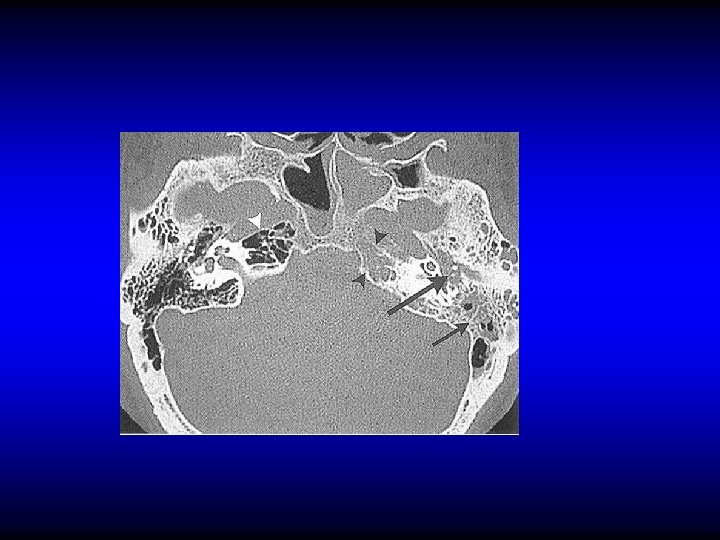

Pathology of labyrinthitis • Labyrinthine fistula – Erosion of the bony labyrinth usually due to cholesteatoma – Mostly in the lateral SCC • Acute labyrinthitis

Diagnosis of labyrinthine fistula • May be asymptomatic • Vertigo • SNHL • Fistula test • CT scan

Treatment of labyrinthine fistula • Mastoidectomy and surgical repair